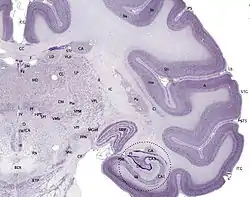

Cortexul cerebral este descris de obicei ca având trei părți: zonele senzoriale, motorii și asociative. Aceste zone senzoriale primesc și procesează informația de la simțuri. Simțurile vederii, auzului și pipăirii sunt deservite de cortexul vizual primar, cortexul auditiv primar și cortexul somatosenzorial primar. Cortexul cerebral este stratul subțire de culoare gri al cerebelului, constând dintr-un strat molecular exterior sau stratum moleculare, un singur strat de celule Purkinje (stratul ganglionic) și un strat granular interior sau stratum granulosum. Cortexul este suprafața exterioară a telencefalului și este compus din materie cenușie.